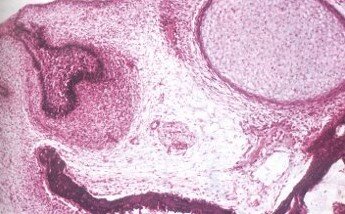

Etapa de campana​

-Campana TEMPRANA

órgano del esmalte 4 capas:​Epitelio externo​, interno o preameloblástico​, Retículo estrellado​ y Estrato intermedio células planas​

Papila dental sin diferenciar​

Saco o folículo dental dos capas: fibrosa y celular​

-Campana AVANZADA

Cambios del órgano del esmalte:​Epitelio externo​, interno o ameloblastos jóvenes​, Retículo estrellado​y estrato intermedio células planas​

Papila dental odontoblastos​